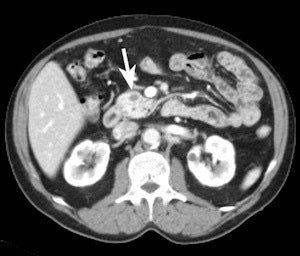

With pancreatic cancer, surgeons need to know if there are any liver metastases because they will usually prevent surgical treatment. Percutaneous biopsies of pancreatic cancer have an inaccuracy rate of up to 25%, so diagnostic imaging plays a central role. The detection of metastases depends on size, histology, and the reaction of contrast agents, and to a lesser extent on the technique, when detecting metastases larger than 2 cm. Accuracy is lower where metastases smaller than 2 cm in size are concerned. Therefore depicting small liver metastases by means of diagnostic imaging before and after contrast administration may avoid unnecessary laparotomies, which are always associated with a different level of morbidity and mortality.

The oncological issue of infiltration affects pancreatic tumors in particular. When assessing preoperative tumor respectability, the most frequent and important question for the surgeon is the relationship between the tumor and the adjacent vessel in order to understand whether the tumor can be separated from it, Manfredi explained. When fat can be detected between the vessel and the tumor, the tumor can be resected, but when the vessel is totally encased by the tumor, it can't. These two extreme examples represent the relatively easy cases, but in the majority of cases in which there is contact between the vessel and the tumor, it is difficult to preoperatively predict whether the surgeon will be able to pass his or her finger between the two, enabling resection, he noted.